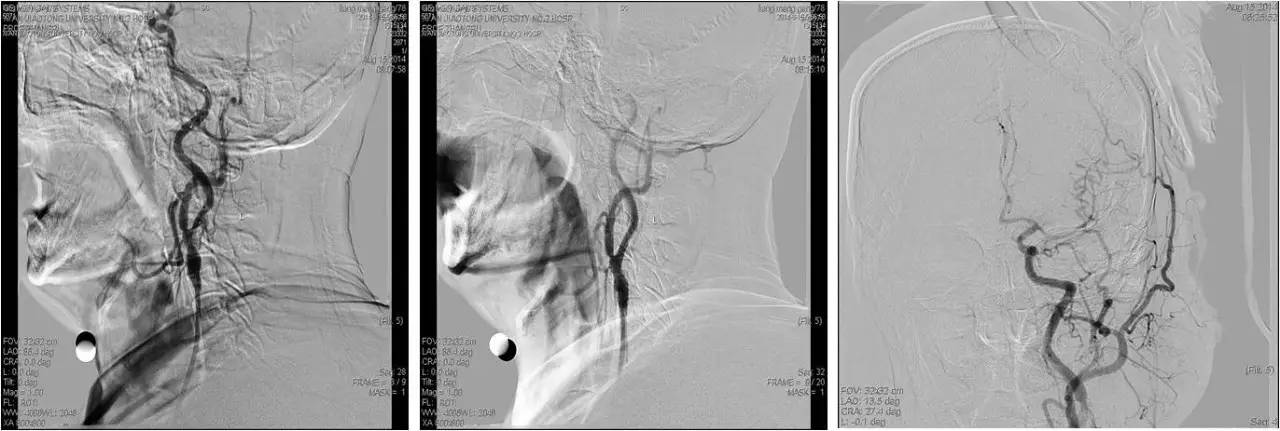

》急诊行DSA+动静脉联合溶栓+左侧颈内动脉狭窄球扩及支架成形术;

》DSA:双侧颈内动脉起始部狭窄,狭窄率约80%,左侧大脑中前动脉显影差继而行超选择左侧颈内动脉动脉溶栓(rt-PA 5mg 推注),远端显影改善,行左侧颈内动脉狭窄球囊扩张及支架成形术。

②DSA 示患侧锁骨下动脉严重狭窄甚至闭塞;

③术后CHS为颅内病变。